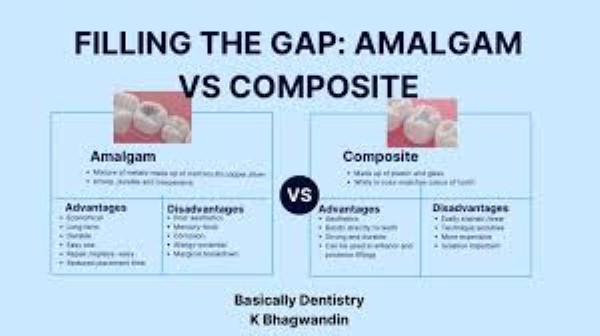

تا همین دهها سال پیش، اگر دندانی میشکست یا جای پوسیدگی بزرگی روی آن بهوجود میآمد، فقط دو راه وجود داشت: یا فلز بگذاریم یا دندان را بتراشیم و روکش کنیم. فلز هم ظاهر خوبی نداشت، هم بعضیها به آن حساسیت میکردند. بعد از دهه ۱۹۶۰، دانشمندان تصمیم گرفتند مادهای بسازند که هم رنگ دندان باشد، هم چسبنده و هم مقاوم؛ مادهای که بتواند جای فلز را بگیرد. از این ایده، کامپوزیت دندانی بهدنیا آمد. امروزه کامپوزیتها آنقدر پیشرفته شدهاند که میتوان با آنها لبخند کامل ساخت، بدون اینکه لازم باشد زیاد دندان را تراشید.

کامپوزیت ترکیبی از رزین نرم و ذرات ریز شیشه یا سرامیک است. رزین، خمیرمایه اصلی است و ذرات، استحکام و رنگ طبیعی را میدهند. وقتی این خمیر روی دندان گذاشته میشود، با نور آبی خاصی سفت میشود؛ مثل خمیری که زیر نور خورشید خشک شود.

مزایایی که باعث محبوبیت شدهاند

ظاهر طبیعی

طیف رنگی گستردهای دارد؛ دندانپزشک میتواند دقیقاً همان رنگ دندان کناری را دربیاورد.تراش کم

در بسیاری موارد، فقط لایه نازکی از مینا برداشته میشود یا اصلاً نیازی به تراش نیست؛ بنابراین ساختار دندان حفظ میشود.یکجلسهای

بیشتر ترمیمها در همان روز اول انجام میشود و نیازی به قالبگیری یا آزمایشگاه ندارد.قابل تعمیر

اگر تراش خورد یا لبپریدگی ایجاد شد، همان نقطه ترمیم میشود و لازم نیست کل کار عوض گردد.هزینه مناسب

در مقایسه با لمینت سرامیکی یا روکش، کامپوزیت ارزانتر تمام میشود.عدم حساسیت دمایی

بیمار معمولاً بعد از کار، نسبت به سرما یا گرما حساس نمیشود.

معایب و محدودیتها

ممکن است رنگ بگیرد؛ مخصوصاً در سیگاریها یا کسانی که زیاد قهوه میخورند.

عمر کوتاهتر نسبت به سرامیک یا روکش دارد.

در نواحی فشار خیلی زیاد (مثلاً دندانهایی که شبها روی هم فشار میآورند) ممکن است بشکند.

به تکنیک حساس است؛ اگر سطح خیس باشد یا لایهگذاری درست انجام نشود، زود جدا میشود.